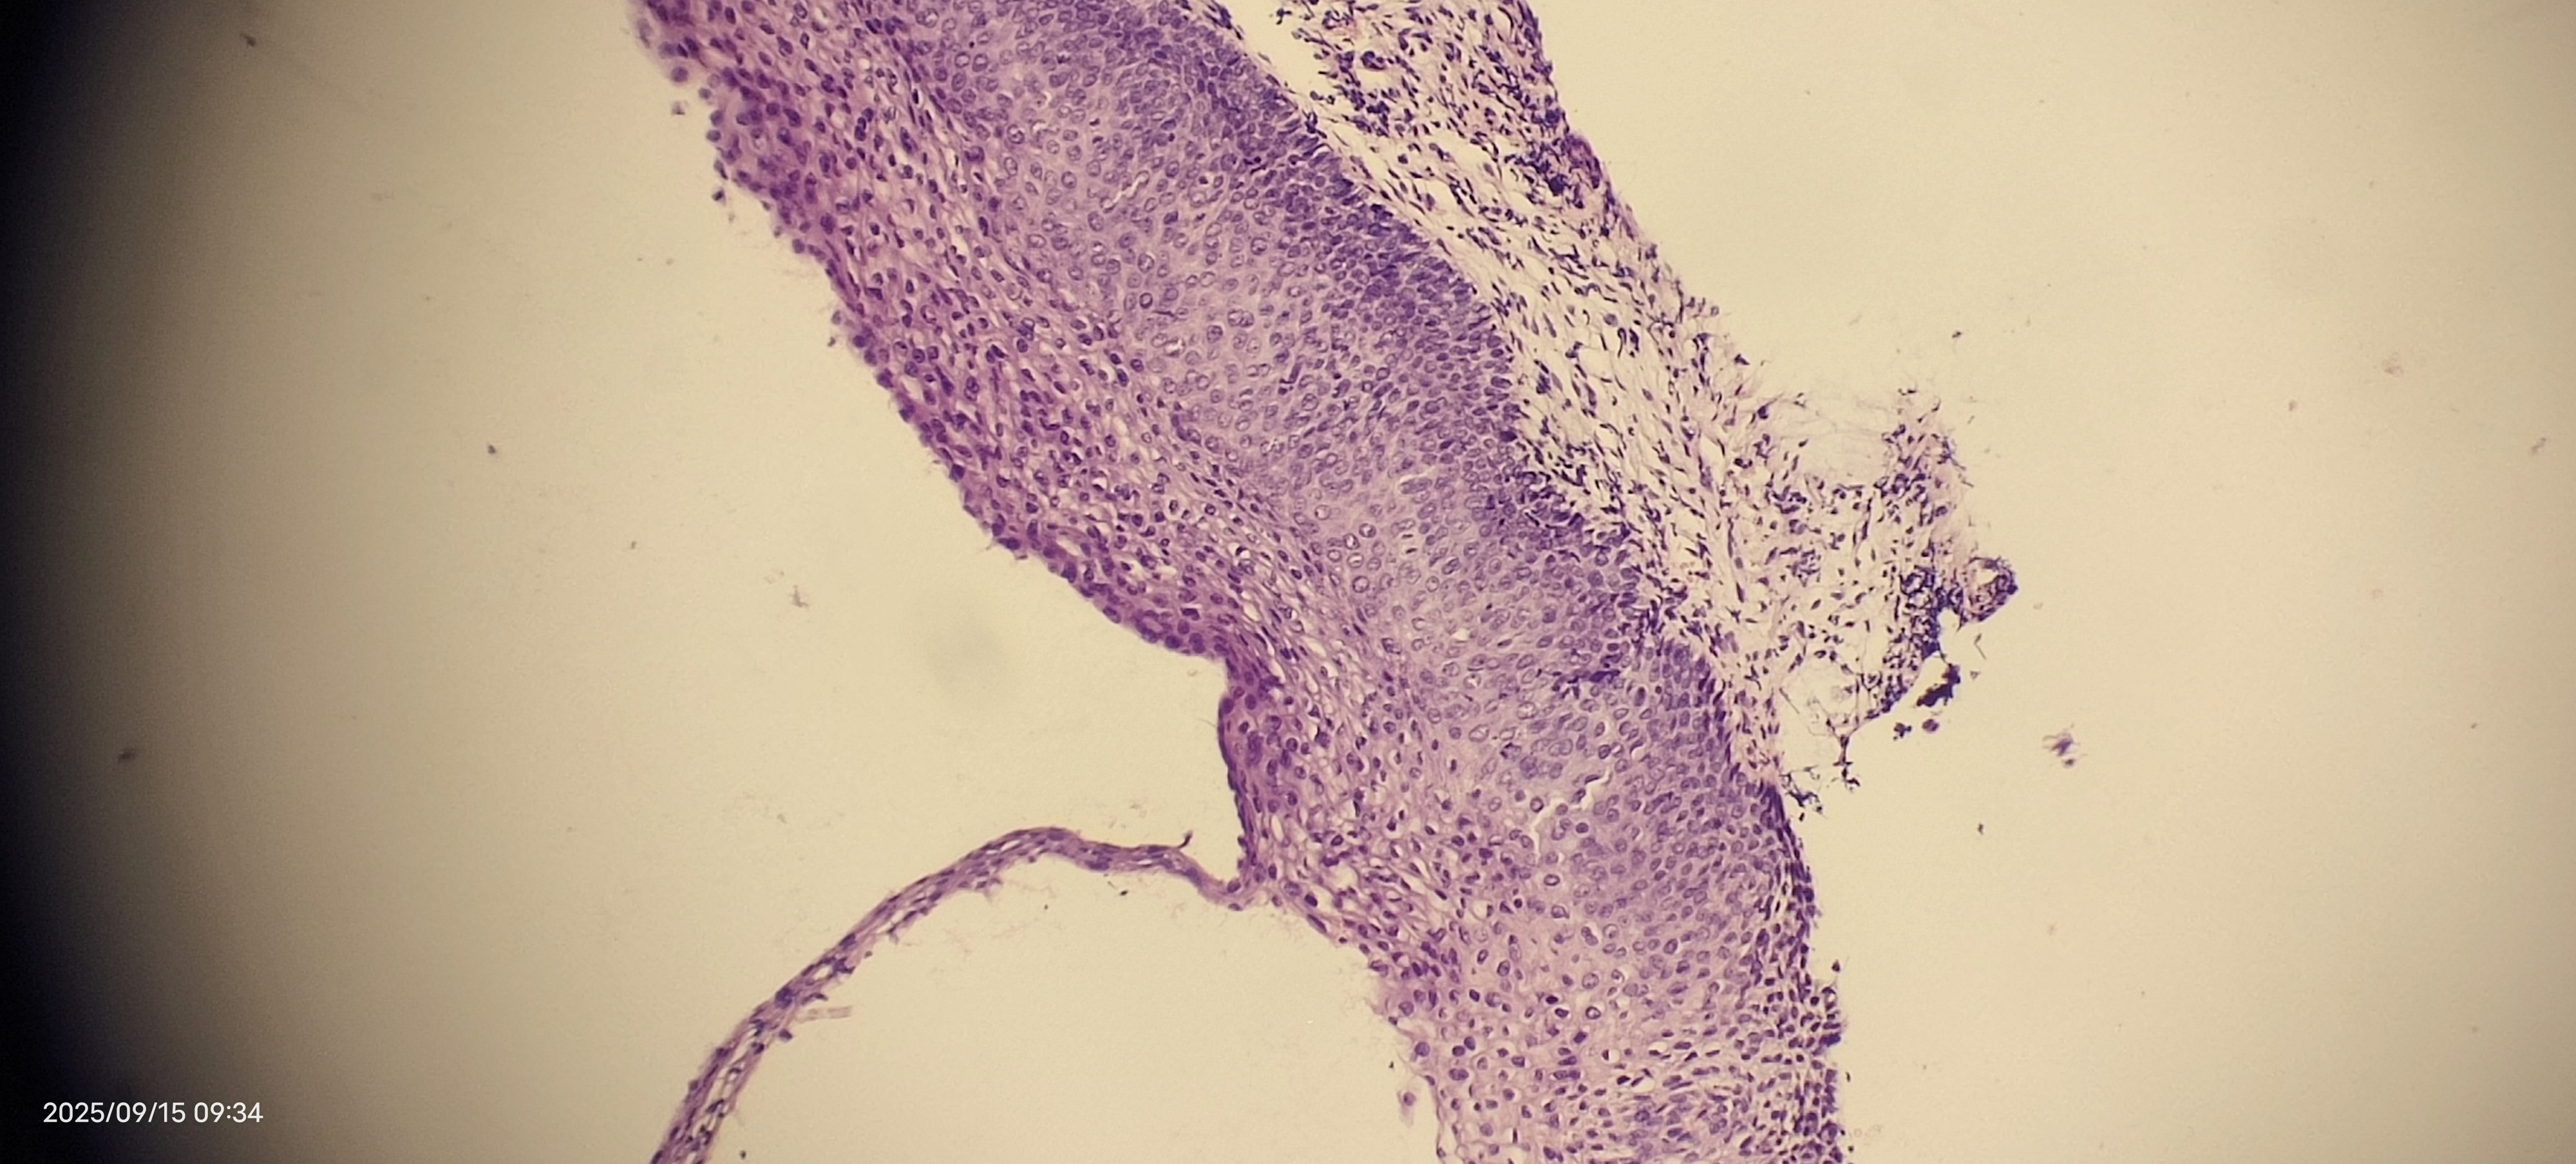

够CIN2级吗

性别

女

年龄

39岁

临床诊断

一般病史

细胞学低级别

标本名称

宫颈活检

大体所见

无

39岁,细胞学低级别 ,最后两张为KI67和P16

图1

图2

图3

图4

图5

CIN1

支持。